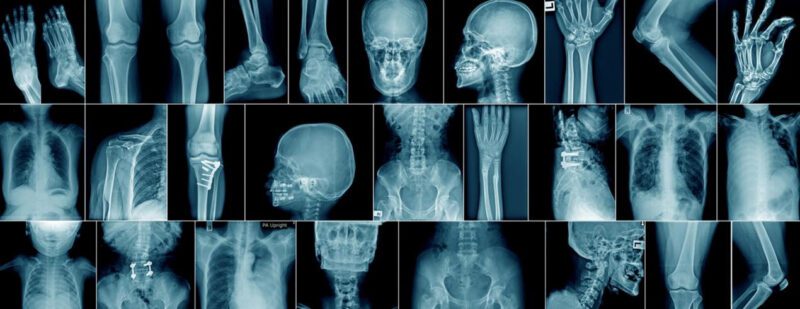

ويستهدف الهاكاثون الذي يستمر لثلاثة أيام المهتمين والمختصين في مجالي الذكاء الاصطناعي والصحة العامة، ويشارك فيه أكثر من 40 متسابقًا ومتسابقة، تحت إشراف خبراء ومختصين من سدايا وجامعة ستانفورد، في سبيل إيجاد حلول تقنية متقدمة تساعد في تشخيص ومعالجة الأمراض باستخدام أنماط بيانات مختلفة.

هذا وقد أقامت أكاديمية (سدايا) على هامش الهاكاثون ورش تدريبية في موضوعات مختلفة منها “تقصي التحيزات في تشخيصات الذكاء الاصطناعي في الحالات الجلدية”، “دمج البيانات متعددة الوسائط ومتعددة النطاق من علوم الأوميكس المتعددة في الطب الدقيق” وتصوير الجينوم “حالة دمج البيانات ودراسة حالة تصلب الشرايين”، و “نموذج أساسي طبي ومجموعة بيانات كبيرة من الصور الطبية” قدمها خبراء من سدايا وجامعة ستانفورد.